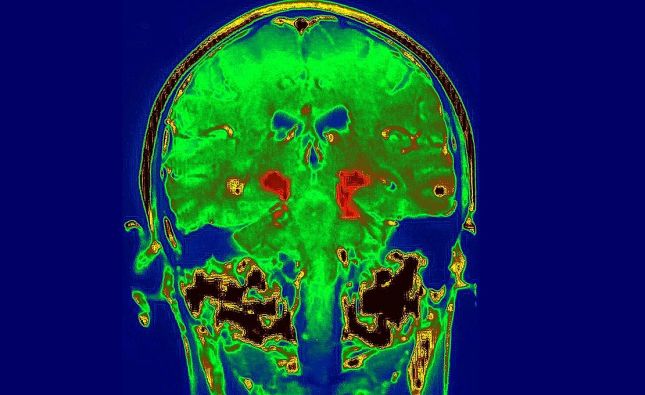

Международно изследване идентифицира специфична мозъчна мрежа като основен механизъм зад развитието на болестта на Паркинсон. Откритието показва, че когато тази мрежа стане прекалено свързана, тя нарушава не само движението, но и мисленето и редица други телесни функции.

Става дума за т.нар. сомато-когнитивна мрежа за действие (SCAN), описана за първи път през 2023 г. от екип на Медицинския факултет на Вашингтонския университет в Сейнт Луис. В новото проучване учените установяват, че SCAN представлява неврологичната основа на болестта на Паркинсон.

Изследването показва, че заболяването се характеризира с прекомерна свързаност между SCAN и подкората – област на мозъка, отговорна за емоции, памет и двигателен контрол. Тази хиперсвързаност води до типичните симптоми на Паркинсон – тремор, затруднено движение, нарушения на съня и когнитивен спад.

Проучването, публикувано на 4 февруари в списание Nature, оспорва дългогодишното схващане, че болестта на Паркинсон засяга основно базалните ганглии, и насочва към по-широка мрежова дисфункция в мозъка.